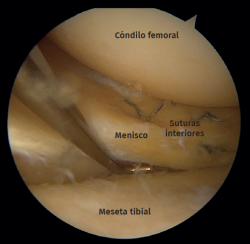

Figure 2. Right knee, Schatzker II tibial plateau fracture. Step-off arthroscopic view from the anteromedial portal. Probe placed in the anterolateral portal.

Standard anterolateral and anteromedial portals are created adjacent to the patellar tendon and the joint is visualized with a 30° arthroscope while the knee is insufflated with normal saline. A diagnostic arthroscopy is performed to confirm the TPF, the step-off and the presence of associated lesions (Figure 2). An arthroscopic shaver is inserted into the knee to clear the debris and improve visualization. Next, a small longitudinal anterolateral skin approach is performed, and the fractures are fixed with cancellous screws and/or a buttress plate applied on the external side (minimally invasive plate osteosynthesis), according to the type of fracture diagnosed (Figure 3). Arthroscopy is used to assist reduction and, when needed, to treat soft tissue injuries. The senior authors prefer to perform meniscal repair or partial meniscectomy before bone fixation due to the better visualization of the meniscus. Conversely, ligamentous reconstructions are performed after arthroscopically assisted fixation to ensure bony stability.